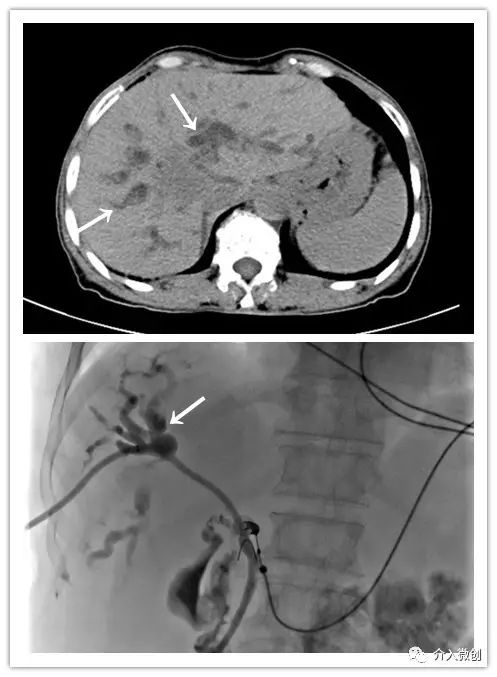

肝动脉化疗栓塞+经皮瘤内注药联合控制肝脏肿瘤

肿瘤侵犯肝门部胆管汇合区

肿瘤侵犯压迫肝门部胆管导致胆道梗阻,置入胆道引流管行胆汁引流减黄